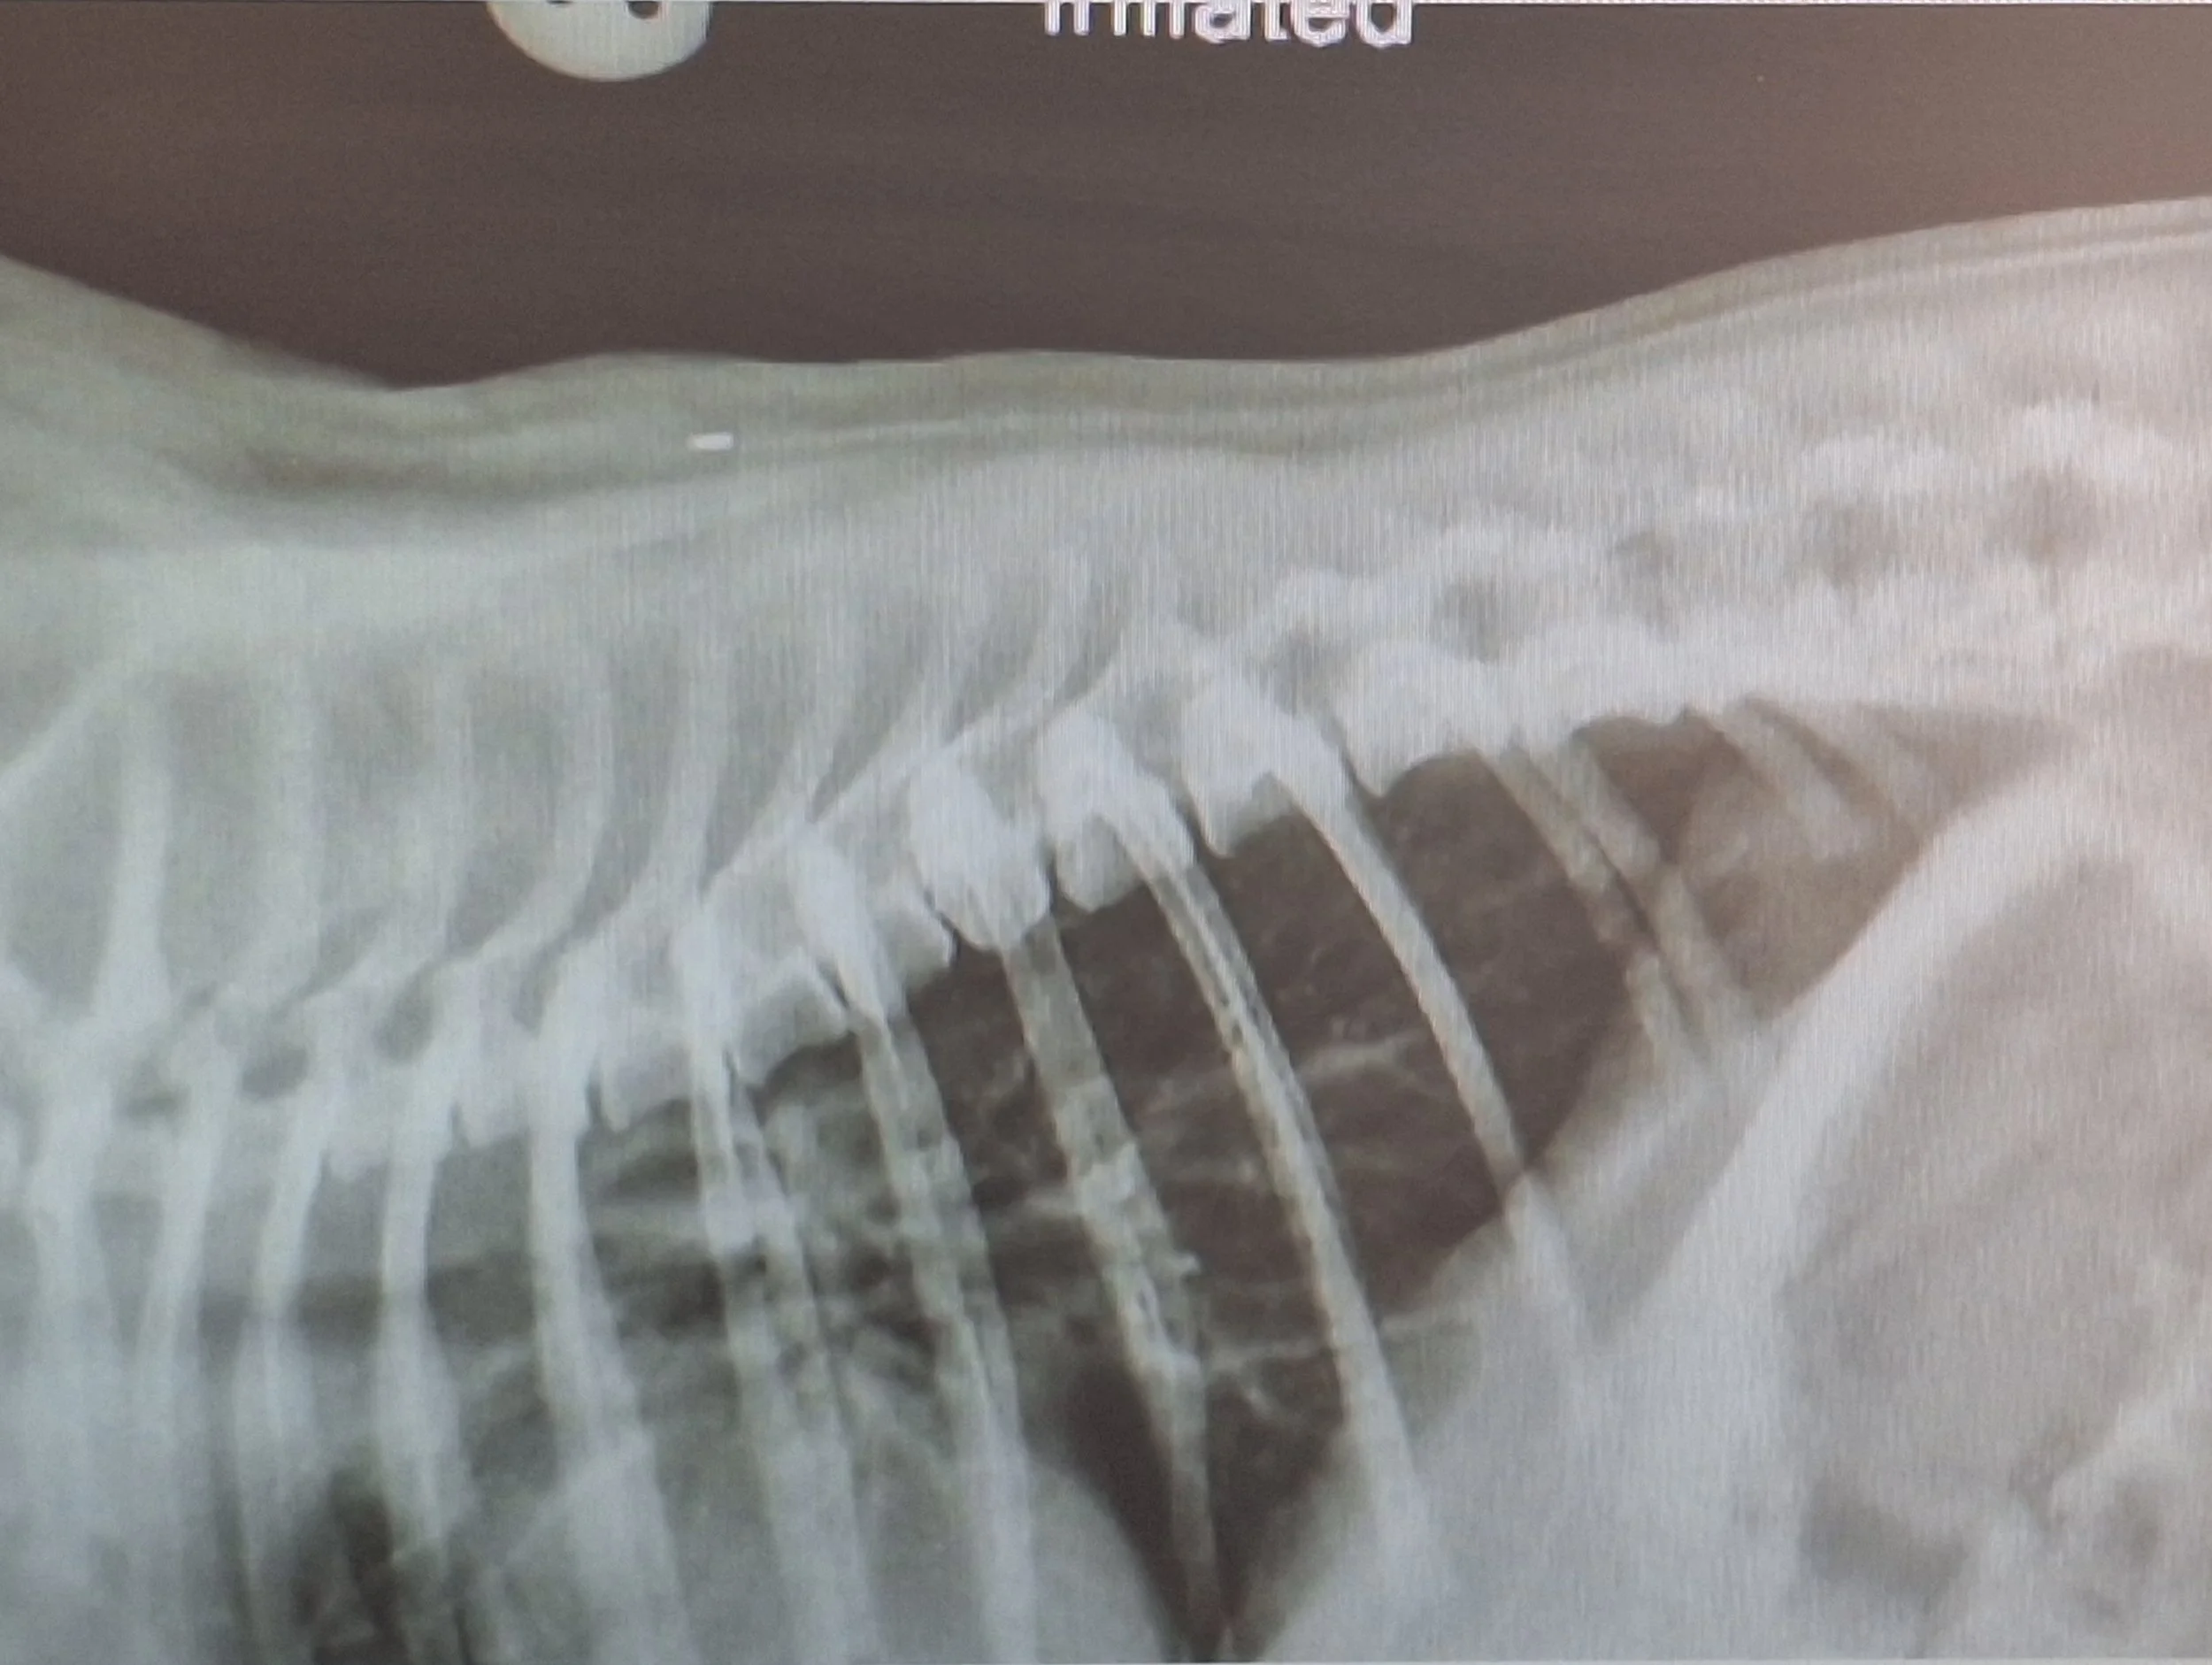

Hemivertebrae

Hemivertebrae is thought to be an inherited condition, though environmental factors may influence it's development. Hemivertebra is when the vertebra has developed abnormally and it is an abnormal wedge shape. This then doesn't allow the spine to align correctly with the adjoining vertebra. This can lead to instability and deformity of the spinal column, this in tern can lead to the spinal cord or nerves being damaged. Signs seen with hemivertebrae are the result of spinal deformity and damage to the spinal cord. They can include pain, ataxia on the hind legs.

Affected dogs can also lose function in their hind limbs and sometimes become incontinent. Not all animals with hemivertebrae develop these signs, some milder and some with no signs at all.